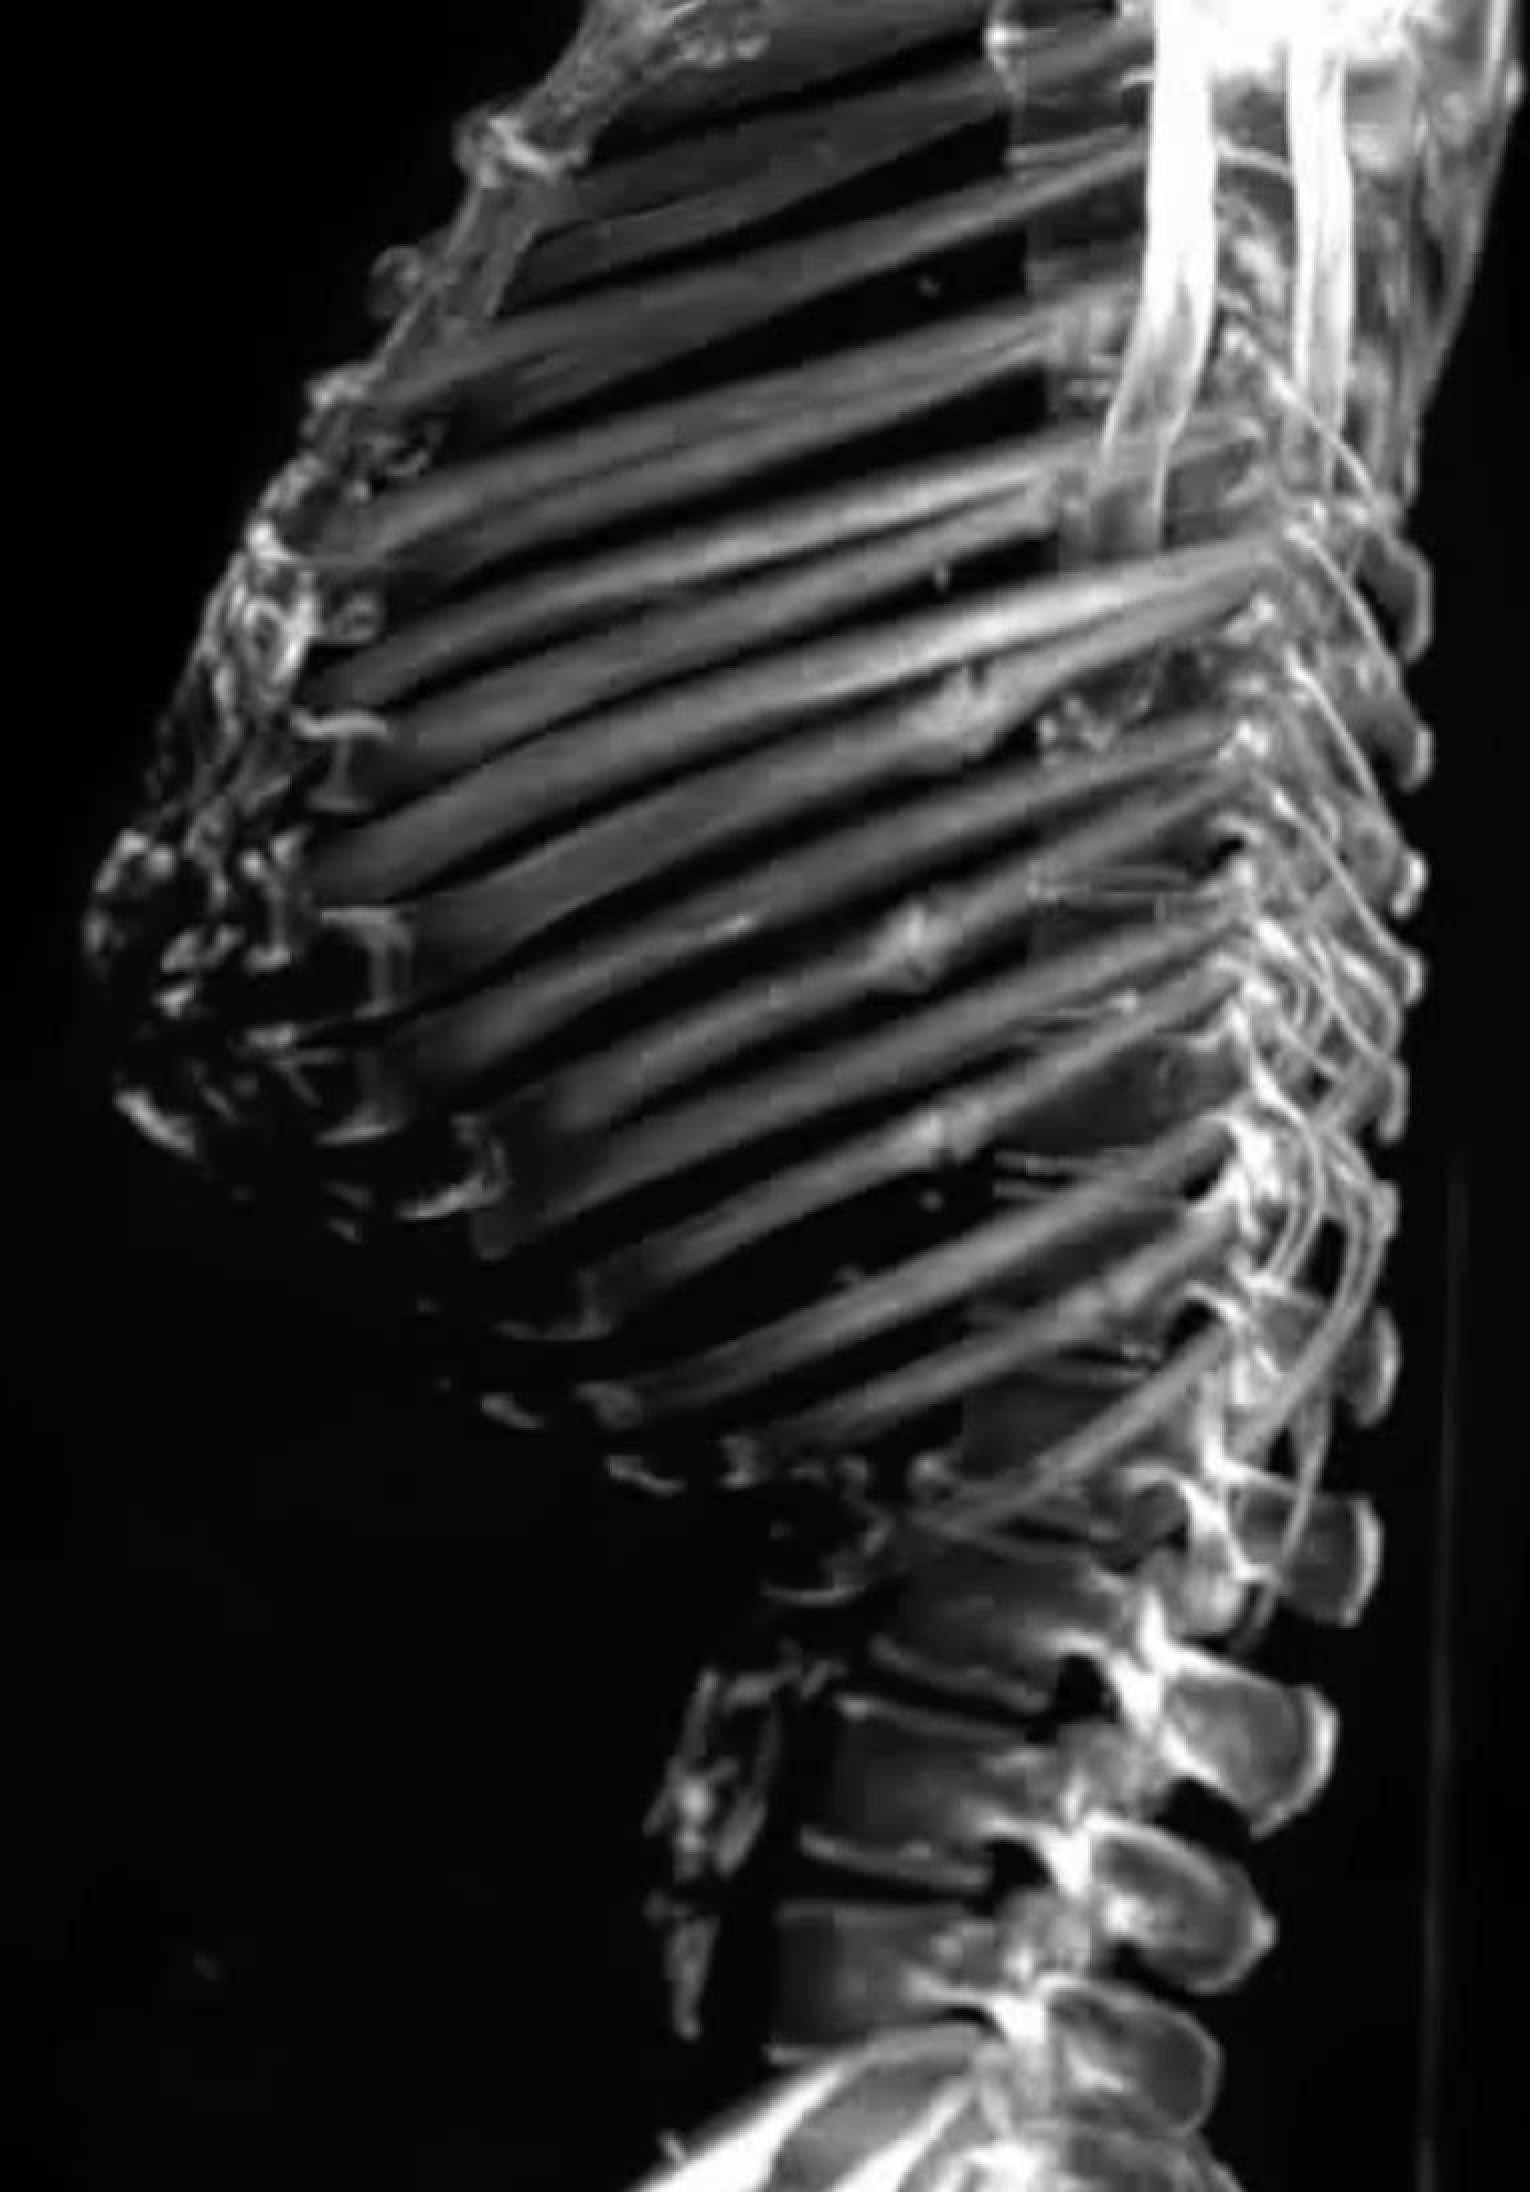

Neueste Technologie in der intraoperativen Bildgebung

Diese Methode ist insbesondere bei komplexen Operationen von großem Vorteil, da sie eine genauere Überwachung des chirurgischen Eingriffs ermöglicht. Zudem können im Verlauf der Operation wichtige Informationen und Daten erhoben werden, die für die weitere Behandlung von großer Bedeutung sind.